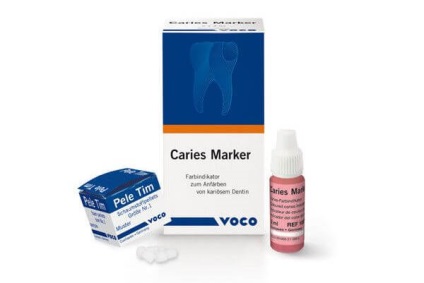

Dintre toate produsele, cea mai mare cerere este pentru indicatori ai următoarelor societăți:

- Voco. 3ml german de cumpărare de droguri, care va costa 1000 de ruble;